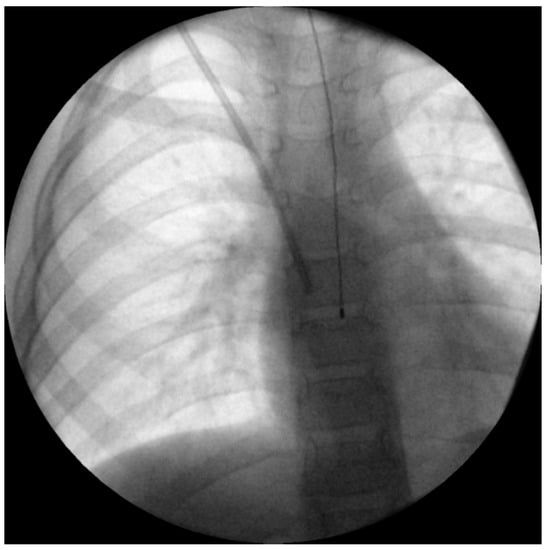

Although the best single estimate of core temperature is considered the pulmonary artery [], its approach is completely invasive, and hence not suitable for children undergoing non-cardiac surgery. A more commonly used alternative is an oesophageal temperature probe [,]. Inserting the probe deep enough to reach the lower third of the oesophagus is important to accurately estimate core temperature []. Correctly placed, it lies directly between the left atrium and the descending aorta, and is therefore far away from the potentially cooling airway (Figure 2). Insertion depth formulas for children such as those of Whitby et al. [] or Hong et al. [] can help estimate the appropriate insertion depth (Table 1).

Figure 2. Intraoperative X-ray of a 6-year-old boy undergoing Broviac catheter implantation with appropriate depth of oesophageal temperature probe inserted, according to the estimation method by Whitby et al. [].